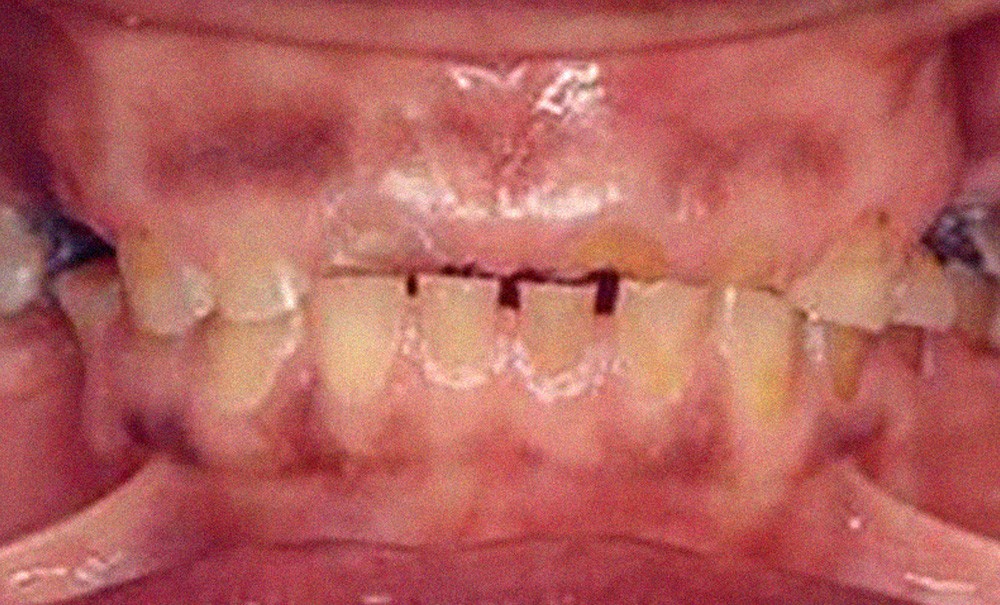

Comme toute parafonction, le bruxisme a des répercussions sur l’organisme et plus particulièrement sur l’appareil manducateur, principal site de son action. Les usures dentaires engendrées peuvent être très variées. Rozencweig distingue quatre stades d’usures [8] :

• stade…